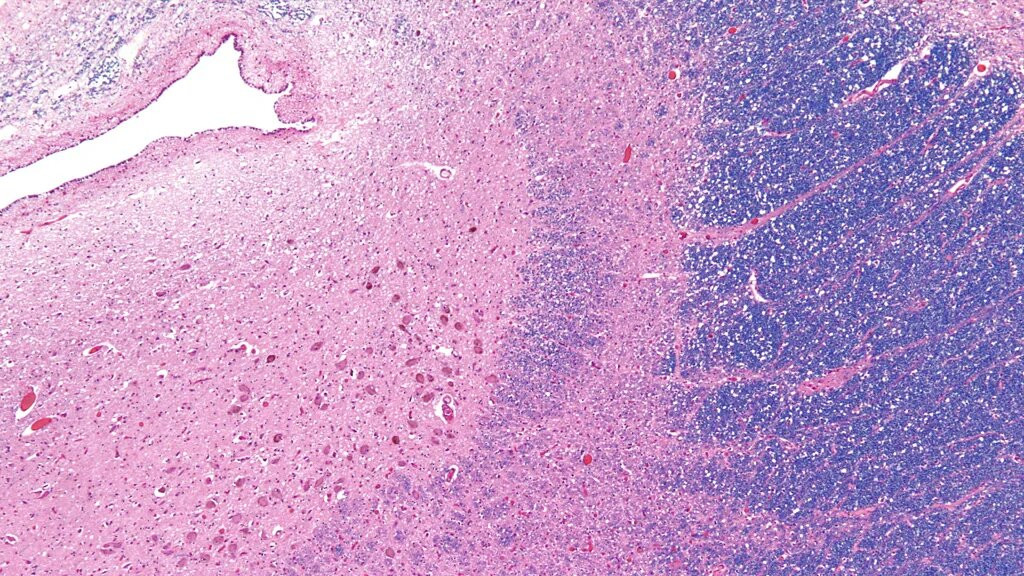

It is a literal description: the neurons in the locus coeruleus are dyed the colour of sapphire from the production of a particular neurotransmitter, called norepinephrine. This is also a clue to the blue dot's function, since norepinephrine controls our physiological and psychological arousal.

The locus coeruleus lies in the brain stem, just above the back of the neck – and contains around 50,000 cells, a tiny portion of the 86 billion neurons in the average central nervous system. Marie Antoinette's physician Félix Vicq d'Azyr was the first to note its existence in the late 18th Century – but for a long time, it failed to attract any further attention.

That began to change in the 20th Century, when it became clear that the locus coeruleus' blue pigment played a key role in brain signalling. Norepinephrine (also known as noradrenaline) raises the chance that a neuron will "spike" with an electric current. When they become active, cells in the locus coeruleus pass bundles of this neurotransmitter along their projections to other regions of the brain – enhancing the communication between the neurons in that area.